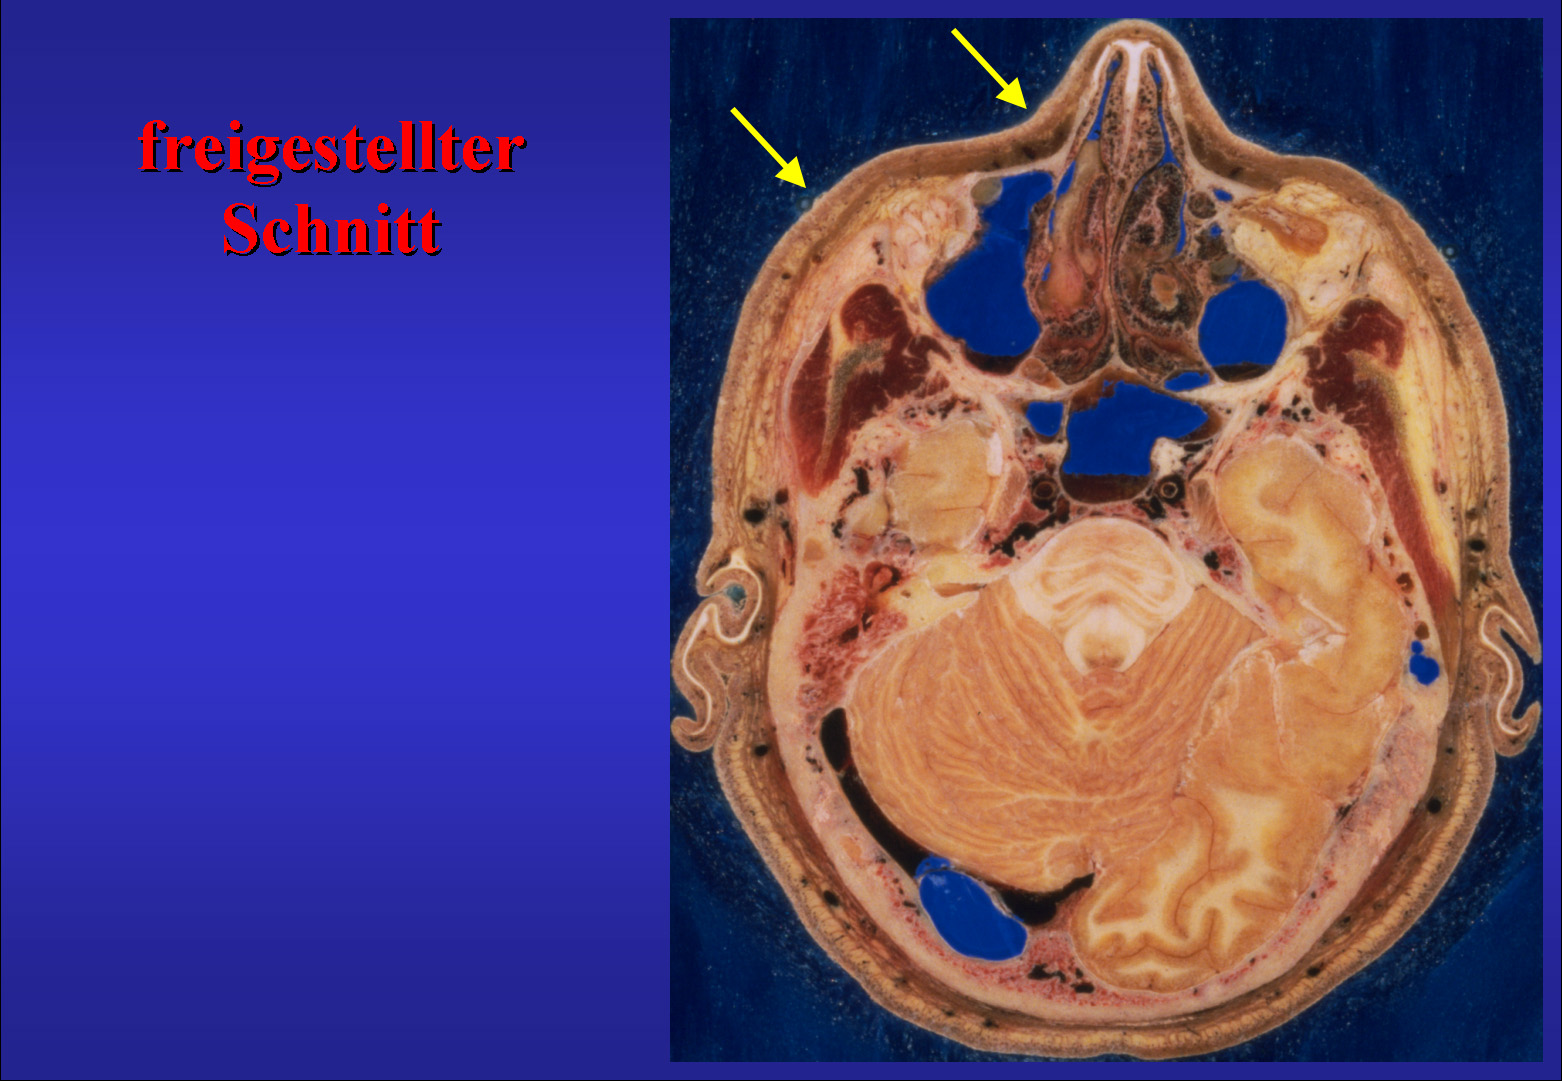

Abb.5

Im Folgenden demonstriere ich Ihnen, wie der Atlas aus den Originaldaten geschaffen wurde. Nach Herunterladen und Entpacken sieht ein Originalschnitt durch den Kopf in Höhe der Nasennebenhöhlen so aus (Abb.5).

Die Schnitte wurden gemäß dem radiologischen Standard orientiert, das heißt man blickt von unten darauf (Abb.6).

Abb.6

Abb.7

Die Schnitte wurden zurechtgeschnitten (Abb.7). Dabei wurde die Originalauflösung erhalten.

Die blaue Füllmasse in Hohlräumen, hier den Nasenebenhöhlen, wurde ausradiert (Abb.9).

Dies geschah mit einem Kopierpinsel wobei Bildinformationen benachbarter oder entsprechender Areale verwendet wurde. Die akkurate digitale Säuberung der Schnitte war der arbeitsaufwendigste Schritt (Abb.10).